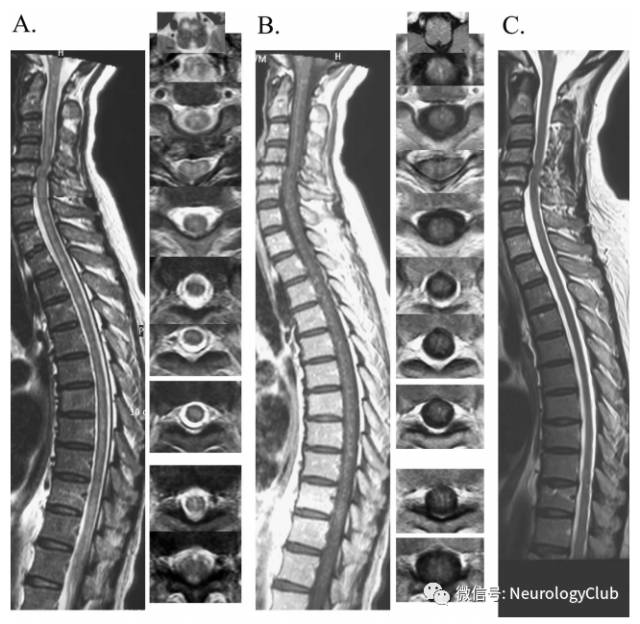

(图27:NBD患者脊髓受累;A:T2WI可见全脊髓多发高信号病灶;B:增强后可见片状强化;C:治疗后病灶基本消失)

(图28:长节段脊髓受累的NBD患者;A:T2WI可见脊髓T3-L2异常信号;B:增强后病灶强化;C:10月后复查可见局部胶质增生不伴强化)

(图29:长节段脊髓受累的NBD患者T2WI横断面可见“百吉饼征”,或与静脉怒张有关,可能为其特征性影像,有助于与其他长节段脊髓病变,如视神经脊髓炎谱系疾病等鉴别